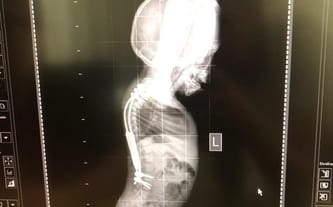

Last summer, Adaś underwent a very complicated spinal surgery. We spent over 6 weeks in the hospital. First, his spine was straightened on a specially prepared extract with the HALO ring and then a special growing bar system was implanted. The results are great. We managed to fund this operation in cooperation with the NFZ.